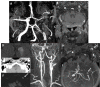

Fig. (2)

There is false double lumen appearance of left petrous ICA on MIP (A) and source (B) views of 3D TOF MRA. Fat suppressed T1 image show crescent sign of hyperintense intramural thrombus, increased external diameter of left ICA with eccentric luminal narrowing (C). Not: intramural thrombus is seen hyperintense on 3D TOF MRA, giving false appearance of double lumen. In another patient with left sided acute striatal stroke (D), arrows show left ICA as enlarged and hyperdense on CT (E) associated with diffusion signal changes on DWI (F). On contrast enhanced neck MRA, flame sign of left ICA is seen with very limited flow distally (arrow on G) and associated enlarged external diameter of left ICA with crescent sign and eccentric luminal narrowing appearing in both source (arrow on H) and MIP (arrow on I) images of 3D-TOF brain MRA. Findings are compatible with dissection of left ICA at the skull base where the enlargement of the vessel is present.